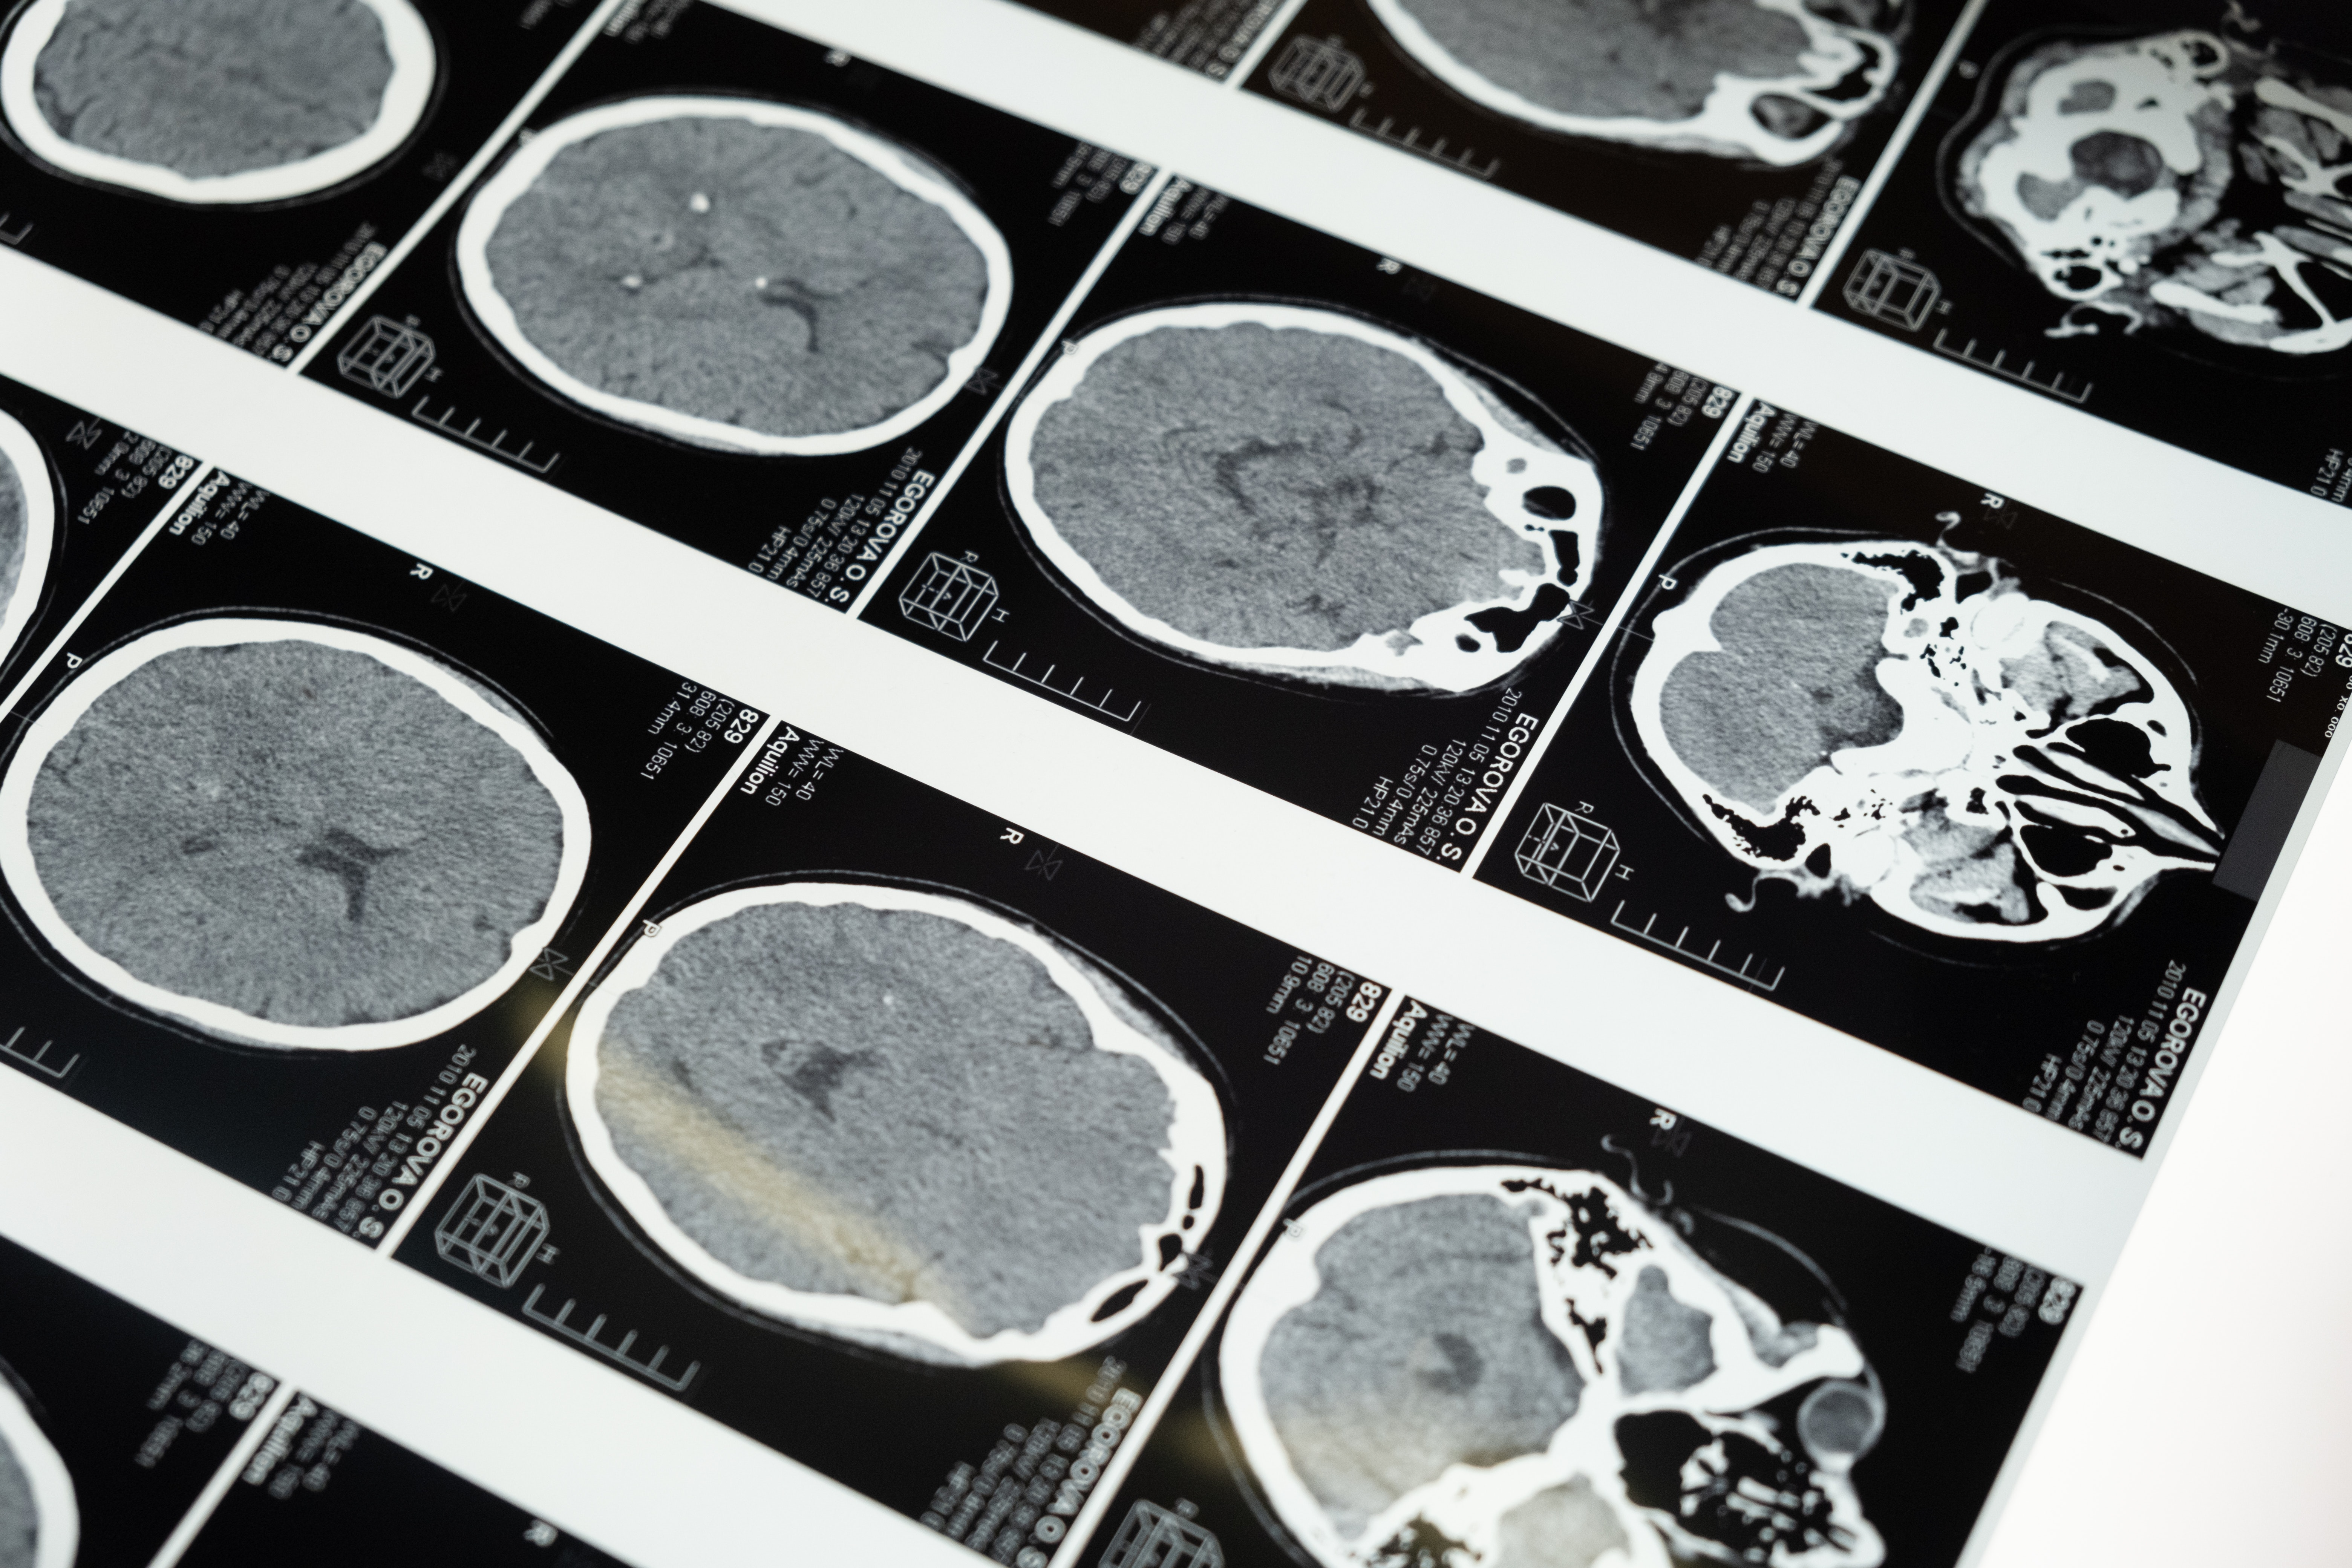

뇌졸중의 이해 : 원인, 증상, 치료 옵션

뇌졸중은 흔히 '뇌발작'으로 불리지만 당장 주의가 필요한 의학적 응급상황이다. 뇌로의 혈류가 끊기거나 감소함으로써 필수 영양소와 산소 결핍으로 이어진다. 뇌졸중은 장애나 죽음을 포함한 심각한 결과를 초래할 수 있다. 다음에서 언급할 내용은 뇌졸중의 원인, 증상, 치료 선택지를 검토하고 이 상태와 적시 개입의 중요성에 대한 포괄적인 이해를 제공하는 것을 목적으로 한다.

뇌졸중의 근본적인 원인을 이해하는 것은 그 발생을 막기 위해 중요하다. 뇌졸중은 여러 요인의 결과일 수 있지만 두 가지 주요 원인은 허혈성 뇌졸중과 출혈성 뇌졸중이다.